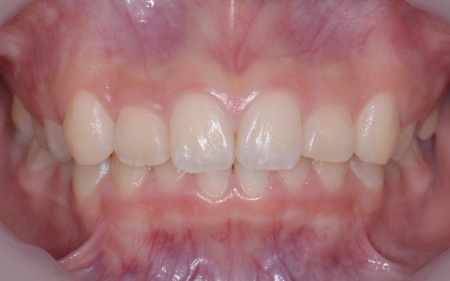

| カウンセリング | 拝見したところ、上の犬歯が歯列の外側に飛び出すように生えている、いわゆる八重歯でした。 さらに、上下の歯全体がデコボコに生えている「叢生(そうせい)」と呼ばれる状態で、これは歯が正しい位置に並ぶためのスペースが不足していることが原因だと考えられます。 このまま放置して顎の成長が完了してから矯正治療を行う場合、歯を並べるスペースを確保することが難しく、永久歯を抜く処置が必要になるケースがあります。 以上のことから、今の段階で歯並びを整える治療が必要だと診断しました。 |

患者様のご家族は「将来的な抜歯はできるだけ避けたいので、今のうちに治療をしたい」と希望されたため、成長期の段階で歯列を広げ、歯が並ぶスペースを確保する小児期の矯正治療「1期矯正」を提案しました。

メリット デメリット また、治療にあたりお口全体のバランスを確認したところ口元の突出はなく、顎のサイズはやや小さめですが、成長期であることから歯列の拡大が可能な状態だと判断しています。 以上の内容について丁寧に説明し、治療に同意いただきました。 まず、上顎に顎の骨を広げるための固定式の矯正器具「急速拡大装置」を、下顎には歯並びの幅を広げるための「リンガルアーチ」を装着します。 次に歯の位置を整えるため、ワイヤー矯正を開始します。 最後に、歯並びが整って見た目や噛み合わせにも問題がないことを確認し、装置を取り外して第1期矯正治療を終了しました。 現在も経過観察を継続していますが、歯が元の位置に戻る後戻りも見られず、残っている乳歯から永久歯への生え変わりも順調に進んでいます。 |